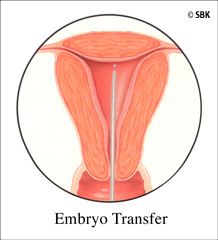

Paso 6: Transferencia (o Implantación) del Embrión: este procedimiento fragil e minimo, es realizado por un doctor que coloca un catéter que fue cargado con una cantidad seleccionada de embriones por el embriólogo, a través del cérvix y dentro del útero para depositar los embriones allí. Cuando es posible, se realizan transferencias de blastocistos, lo cual ocurre alrededor del día cinco del crecimiento embrionario. Las transferencias de blastocistos permiten la implantación de un embrión más maduro, y de esa manera, el embriólogo puede seleccionar menos embriones para transferir, logrando una alta tasa de embarazos con un menor riesgo de gestaciones múltiples superiores a los gemelos. Ocasionalmente, en la etapa de división, el embriólogo recomienda la transferencia en el día tres del crecimiento embrionario basándose en la calidad del embrión.

Paso 6: Transferencia (o Implantación) del Embrión: este procedimiento fragil e minimo, es realizado por un doctor que coloca un catéter que fue cargado con una cantidad seleccionada de embriones por el embriólogo, a través del cérvix y dentro del útero para depositar los embriones allí. Cuando es posible, se realizan transferencias de blastocistos, lo cual ocurre alrededor del día cinco del crecimiento embrionario. Las transferencias de blastocistos permiten la implantación de un embrión más maduro, y de esa manera, el embriólogo puede seleccionar menos embriones para transferir, logrando una alta tasa de embarazos con un menor riesgo de gestaciones múltiples superiores a los gemelos. Ocasionalmente, en la etapa de división, el embriólogo recomienda la transferencia en el día tres del crecimiento embrionario basándose en la calidad del embrión.